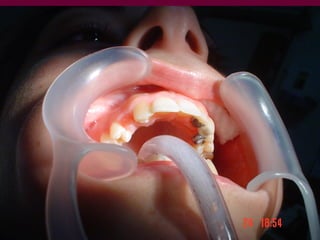

Conocer los diversos recursosprotéticos que dispone la odontología Prótesis fija Prótesis removible parcial Prótesis removible total Prótesis implanto-asistida

SOPORTE es lapropiedad de la prótesis de trasmitir a los tejidos (mucosa-hueso y sistema periodontal) los esfuerzos funcionales sin alteraciones patológicas. Depende de los propios tejidos y de la prótesis en si misma

RETENCIÓN es lacapacidad de la prótesis de oponerse a las fuerzas extrusivas que tienden a desvincularla de su asiento

ESTABILIDAD es lacapacidad de la prótesis de no ser desplazada en sentido lateral por las fuerzas de los tejidos de la cavidad oral (mejillas, labios y lengua) y por la acción funcional

FIJACIÓN incluye las condiciones de soporte, retención y estabilidad y le permite mantener un vínculo permanente con el terreno o volver inmediatamente a él frente a fuerzas que tienden a separarla